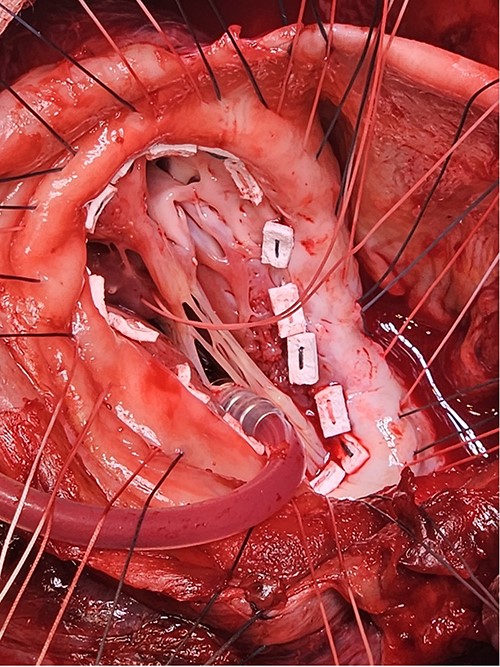

Following median sternotomy, cardiopulmonary bypass was instituted (bicaval drainage, ascending aortic return). Antegrade cardioplegia was delivered with aortic root venting and bicaval snaring. Dense adhesions surrounded the aneurysm, which had a thin wall, measured ⁓15 cm from LV apex to mitral annulus, and contained around 150 g of clot. The posterior mitral leaflet appeared retracted, preventing coaptation due to LV stretching. The aneurysm was resected (Fig. 2), and the LV wall repaired with a 5 × 3 cm patch, restoring normal LV size (Fig. 3). The musculotendinous junctions of the anterior and posterior papillary muscles were approximated using pledgeted 3–0 polypropylene sutures (Fig. 4). The patch repair was completed (Fig. 5), and the overlying sac oversewn for haemostasis.

The LV aneurysm was resected down to its neck into healthy ventricular scar tissue. The posterior chordae can be seen from the ventricular defect.

Pledgeted Ethibond sutures were placed circumferentially around the aneurysm mouth.

Once the sutures for the patch were placed, the two papillary muscles were identified and another pledgeted suture through the musculotendinous junction was used to approximate them.

A: The patch was parachuted down and secured. B: Following this the aneurysm sac was closed over the patch for added haemostasis.